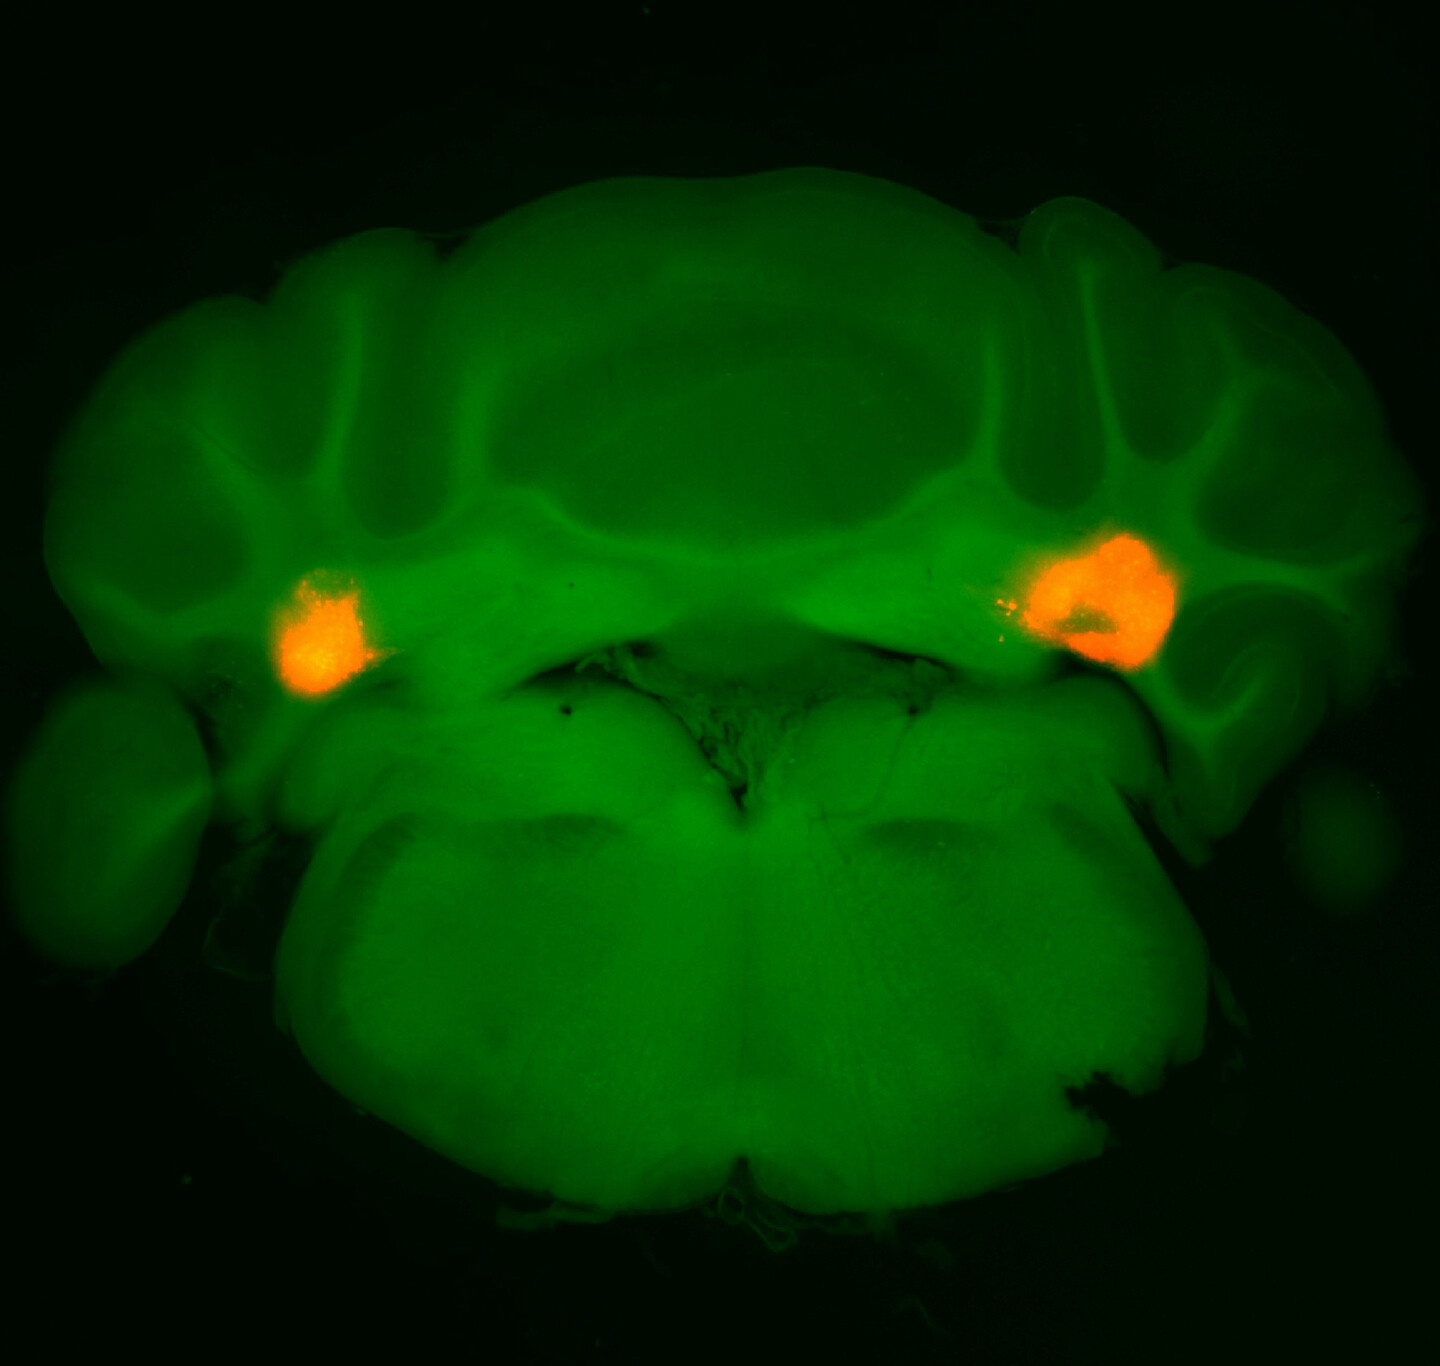

The work, shared in the journal Nature, suggests that neurons in the cerebellum’s anterior deep cerebellar nuclei (aDCN) are involved in helping animals regulate their meal size.

Turning to the mice, single-cell transcriptomic analysis confirmed that a small subset of glutamatergic neurons in the aDCN were the ones being activated upon eating. Activating only these aDCN neurons led the animals to dramatically constrain their meal size, whether they had been deprived of food or given as much food as they wanted previously. When the researchers did the reverse, inhibiting these same neurons, the mice ate larger-than-normal meals. While reducing food intake can often lead people and animals to compensate by eating more food later, the aDCN-stimulated animals did not do so, and measures of metabolic activity remained steady.